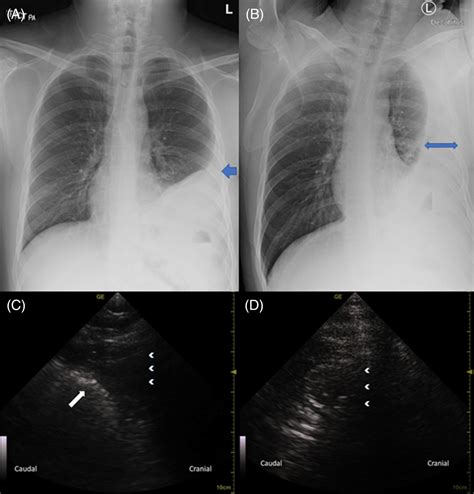

A Rare Case of an Adult Congenital Diaphragmatic Hernia becoming ...